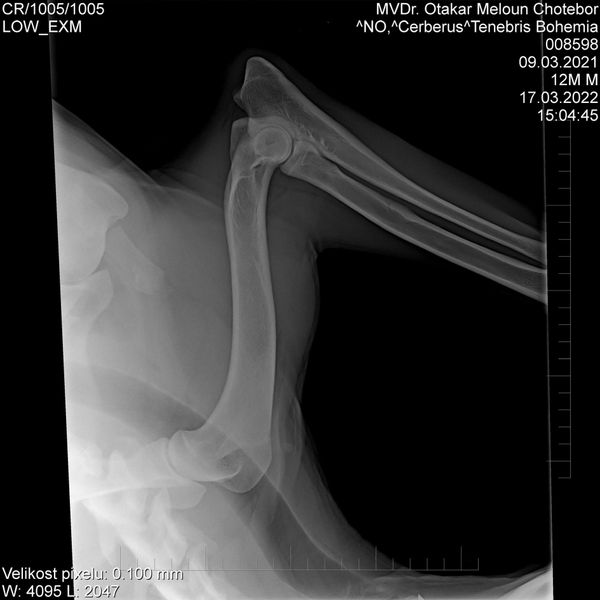

HD: A

ED: 0/0

Spondy: Free